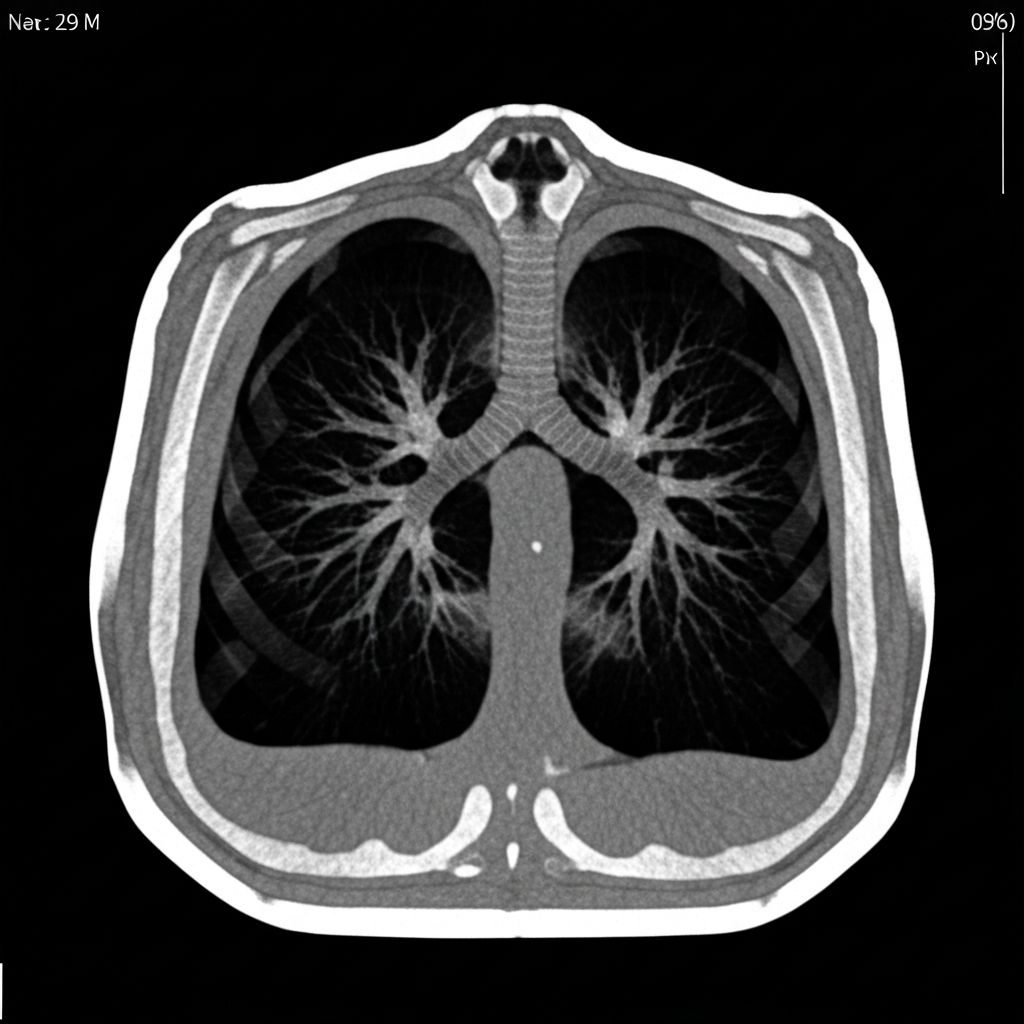

CT CHEST 2024

SLICE 47/128

ZOOM 1.2x